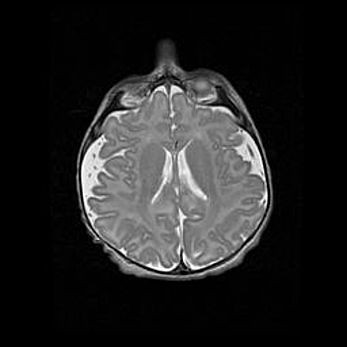

Сообщающаяся гидроцефалия. Кистозная энцефаломаляция головного мозга.

Возраст: 3 месяца 4 дня

Вес: 3100 г

Пол: женский

Окружность головы: 34 см

Срок гестации: 31 неделя

Кистозная энцефаломаляция головного мозга - одна из форм поражения головного мозга в детском возрасте. Характеризуется возникновением множественных и распространённых кист в коре, белом веществе и подкорковых образованиях головного мозга у плодов, новорождённых и детей раннего возраста. Развитие кистозной энцефаломаляции связано с внутриутробной асфиксией и гипотонией, родовой травмой, тромбозом синусов, пороками развития сосудов, инфекциями, сепсисом и другими причинами. Наиболее значимые инфекционные агенты: вирусы простого герпеса, цитомегалии, краснухи, токсоплазмы, энтеробактерии, золотистый стафилококк и другие.